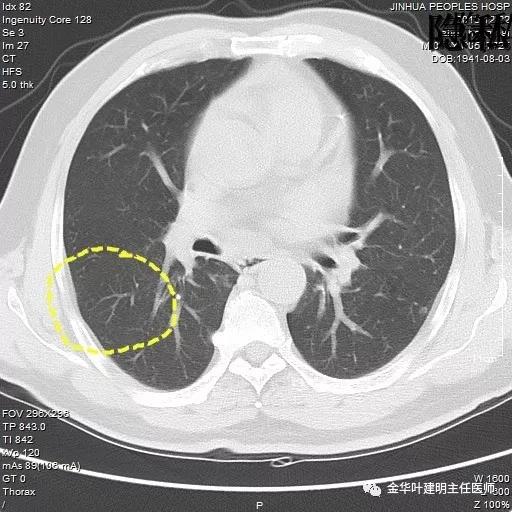

以上是2015年12月的片子,此处没有异常。

以上是2016年5月的片子,此处有非常小而淡的空腔性病灶,边缘略显磨玻璃,但仍说不上肯定的恶性。